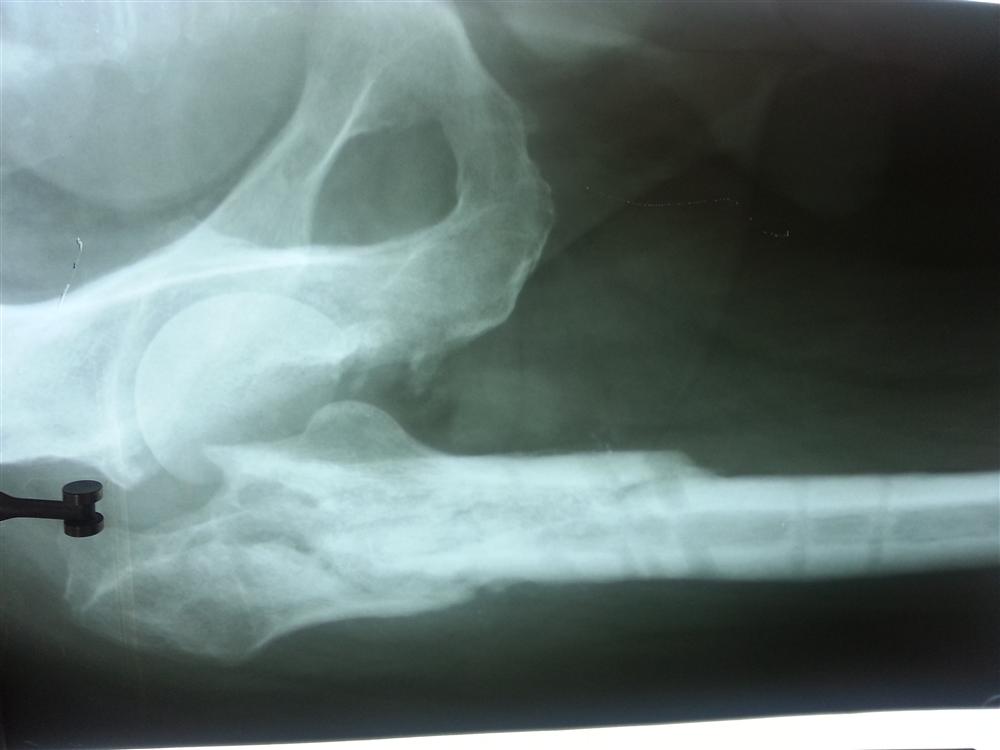

Localization Of Infection Site In Femoral Stabilization Pin Pin Site Infection Orthobullets wound & hardware infection is the most common complication following orthopedic trauma surgery and is a. pin site infection and inflammation one important aspect of care of the patient with an external fixator in situ is the. Pin Site Infection Orthobullets.